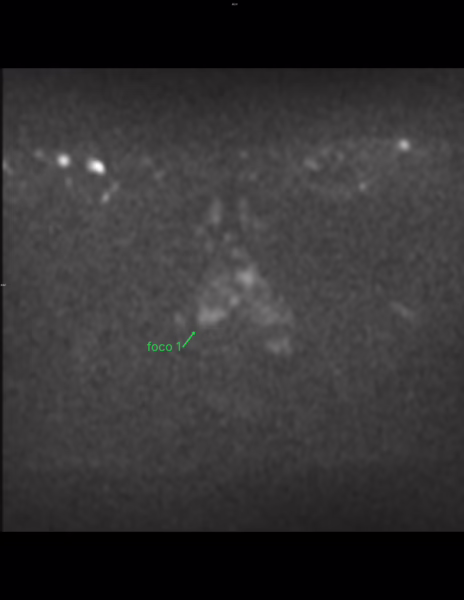

Lesión #1: Mide: aproximadamente 6 mm.

Serie 5, Imagen 22/30.

Localización: Zona periférica posteromedial derecha a nivel apical (sector RA-PZpm).

DWI: Marcada hiperintensidad en difusión y marcada hipointensidad en ADC. Categoría 4/5.

PI-RADS 4

Lesión índice PI-RADS 4 en la zona periférica posteromedial derecha a nivel apical (sector RA-PZpm). Mide aproximadamente 6 mm, con probabilidad 0 de 3 de presentar extensión extraprostática